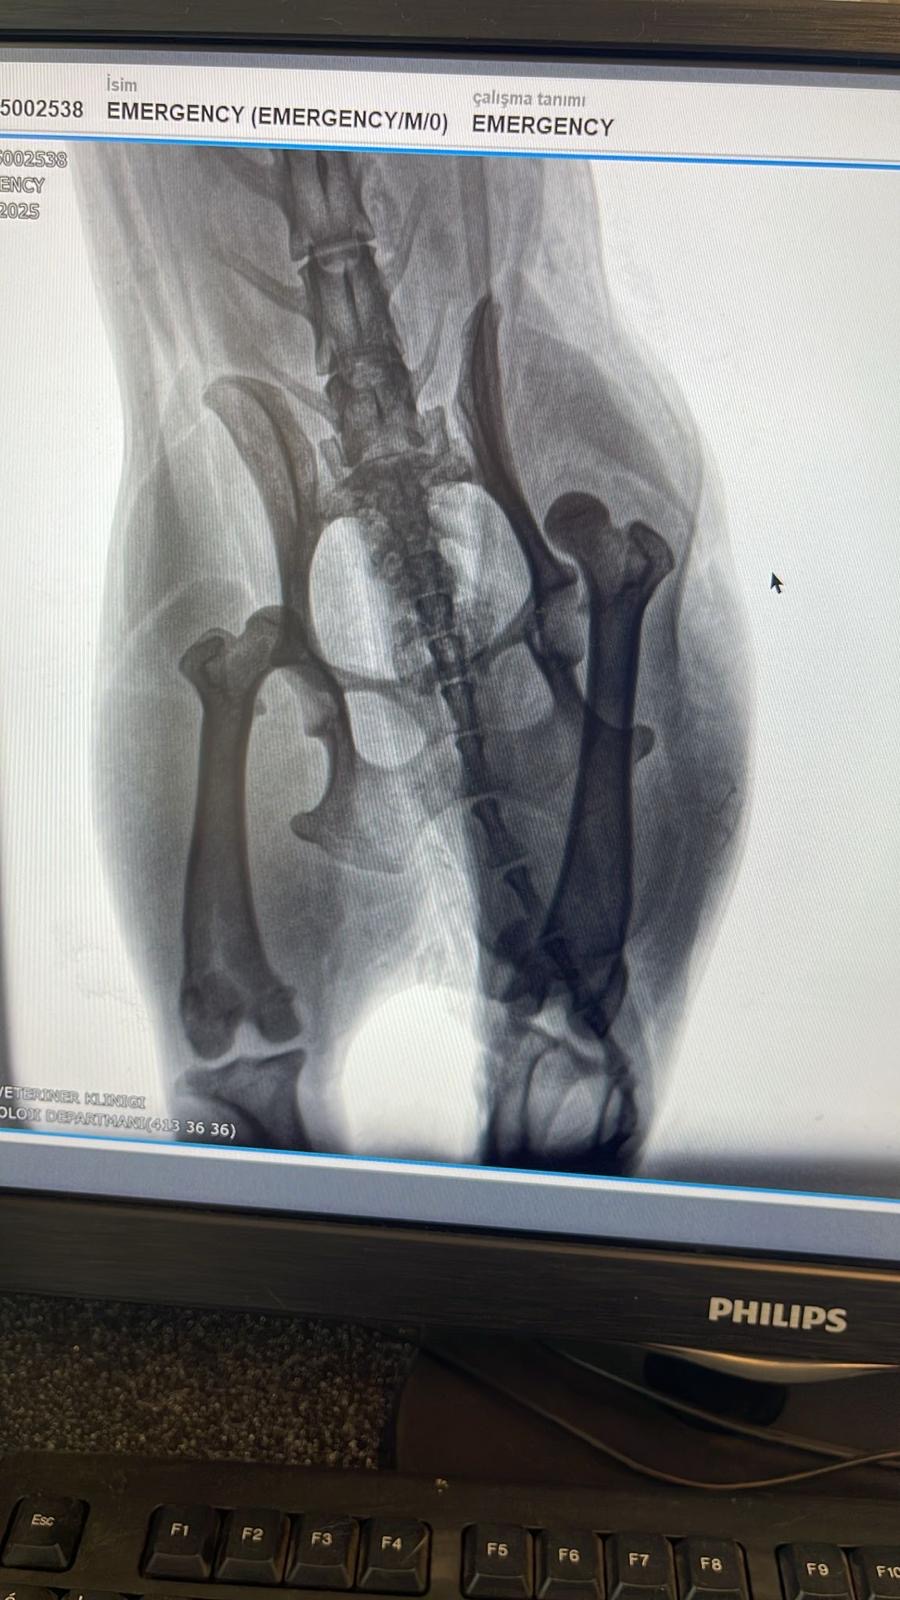

İçmeler Mahallesi’nde bir köpek, yaban domuzlarının saldırısına uğrayarak sakat kaldı.

Köpeğin sahibi, hayvanın bir dizi ameliyat geçirdiğini ve fiziksel olduğu kadar psikolojik olarak da ağır travmalar yaşadığını belirtti. Olay sonrası büyük bir korku ve endişe içinde olduklarını ifade eden sahibi, “Köpeğimiz çok sağlıklıydı, şimdi ise bu hale geldi. Artık her şeyden korkuyoruz,” sözleriyle yaşadıkları mağduriyeti dile getirdi.